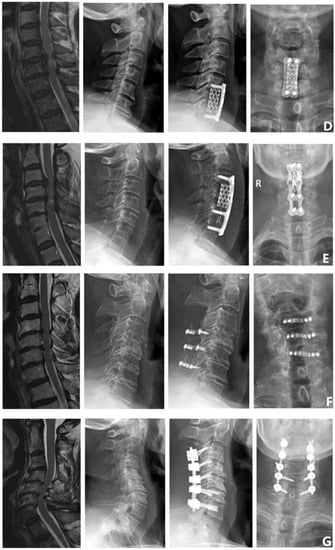

Every patient underwent a pre-operative 3.0 T MRI scan to assess the degree of spinal cord compression, and all the enrolled patients underwent a 3.0 T magnetic resonance imaging (MRI) scan (Siemens Medical Solutions, Erlangen, Germany) pre-operatively. The axial MRI images were aligned parallel to the inferior endplate of the vertebral body. The methods that were used to measure the cervical MRI parameters are detailed in Table 1 and Figure 5. For patients with multilevel DCM, we measured the segment with the most severe spinal cord compression.

Figure 5.

MRI parameter measurement of cervical spine. (A) MSCC. (B) MCC. (C) TA. (D) CR.